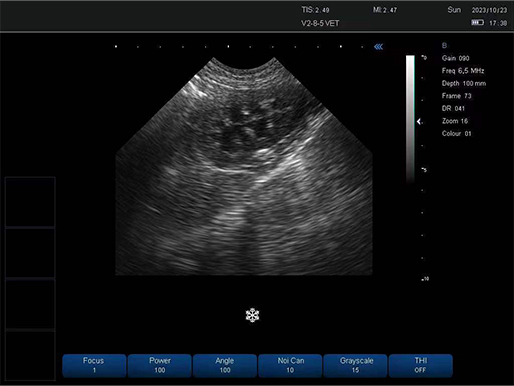

犬 膀胱

犬 膀胱

有关病变的更多见解

凸阵探头-犬 膀胱